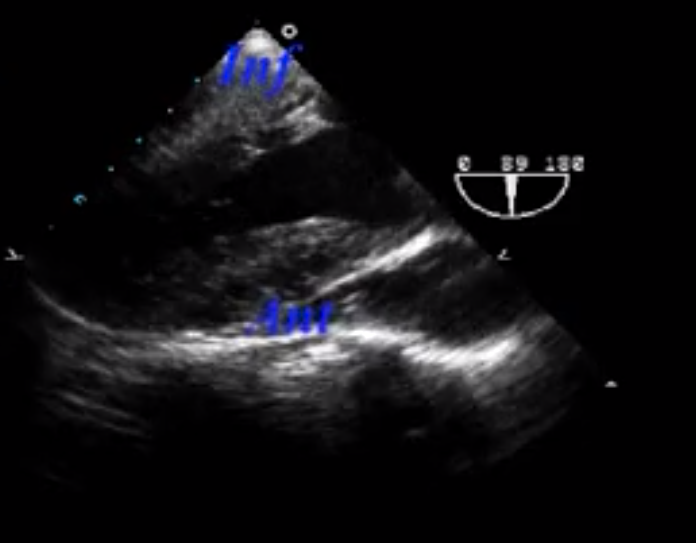

What view is seen here?

Transgastric 2 chamber view

Mitral Valve Subvalvular Apparatus

What walls of the heart are shown here?

INFERIOR = CLOSE TO THE PROBE

ANTERIOR = AWAY FROM THE PROBE

What papillary muscle is seen here?

Posteromedial Papillary Muscle